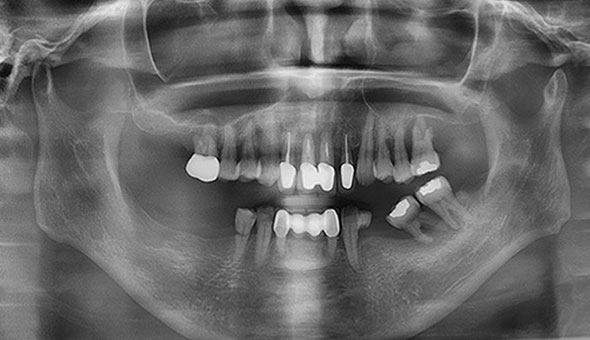

네비게이션 임플란트는 3D CT를 통해 입체 영상으로 정확한 수술 계획을 세우고, CT자료를 기반으로 구강에 끼우는 보조장치를 제작하여 잇몸 절개없이 작은 구멍을 뚫어 임플란트를 식립하여, 잇몸을 절개하는 수술방법보다 통증과 출혈이 적어 비교적 회복이 빠르게 나타납니다.